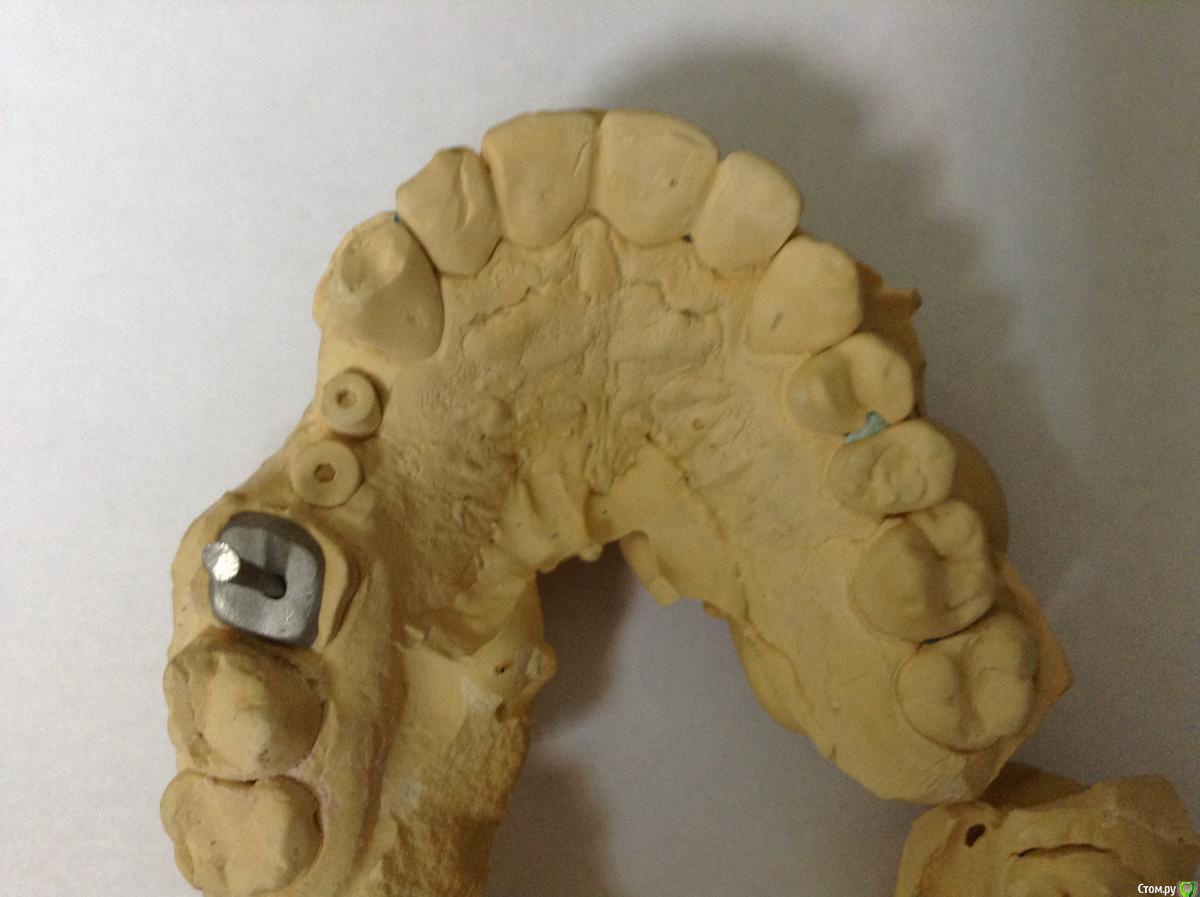

ksenistom Опубликовано 2 декабря, 2014 Поделиться Опубликовано 2 декабря, 2014 Уважаемые коллеги,подскажите пожалуйста,как быть в данной клинической ситуации? Ссылка на комментарий

ksenistom Опубликовано 2 декабря, 2014 Автор Поделиться Опубликовано 2 декабря, 2014 Почему места недостаточно?)) Все получится, даже у среднеграмотного техника. Где одиночка, премолярчик выйдет)Мне хирург так и сказал,только что мне с 6 делать?там все вплотную,расстояние должно 1,5мм минимум быть? Ссылка на комментарий

chernov Опубликовано 2 декабря, 2014 Поделиться Опубликовано 2 декабря, 2014 Мне хирург так и сказал,только что мне с 6 делать?там все вплотную,расстояние должно 1,5мм минимум быть?от чего-до чего,расстояние должно быть?знаете? Ссылка на комментарий

ksenistom Опубликовано 2 декабря, 2014 Автор Поделиться Опубликовано 2 декабря, 2014 от чего-до чего,расстояние должно быть?знаете?От зуба до импланта 1,5мм,между имплантатами 3мм или я ошибаюсь? Ссылка на комментарий

chernov Опубликовано 2 декабря, 2014 Поделиться Опубликовано 2 декабря, 2014 От зуба до импланта 1,5мм,между имплантатами 3мм или я ошибаюсь?1,5мм ширина костной перегородки для формирования сосочка,а конструктивно(для техника) разницы нет. Ссылка на комментарий

chernov Опубликовано 2 декабря, 2014 Поделиться Опубликовано 2 декабря, 2014 (изменено) То есть в данной ситуации достаточно места для протезирования?в технической части-да,достаточно,а с эстетикой могут возникнуть проблемы. Изменено 2 декабря, 2014 пользователем chernov Ссылка на комментарий

togrul Опубликовано 2 декабря, 2014 Поделиться Опубликовано 2 декабря, 2014 В данной ситуации лучше сделать на стандартных абатментах , места мало между имплантатами гигиена будет страдать. Ссылка на комментарий

Евгений Ходыкин Опубликовано 3 декабря, 2014 Поделиться Опубликовано 3 декабря, 2014 Делайте в блоке премоляры, техники размоделировать смогут. Про эстетику забыть... Ссылка на комментарий

ksenistom Опубликовано 3 декабря, 2014 Автор Поделиться Опубликовано 3 декабря, 2014 Делайте в блоке премоляры, техники размоделировать смогут. Про эстетику забыть...Премоляры я поняла,что в блоке,спасибо))а что делать с одиночкой? Ссылка на комментарий